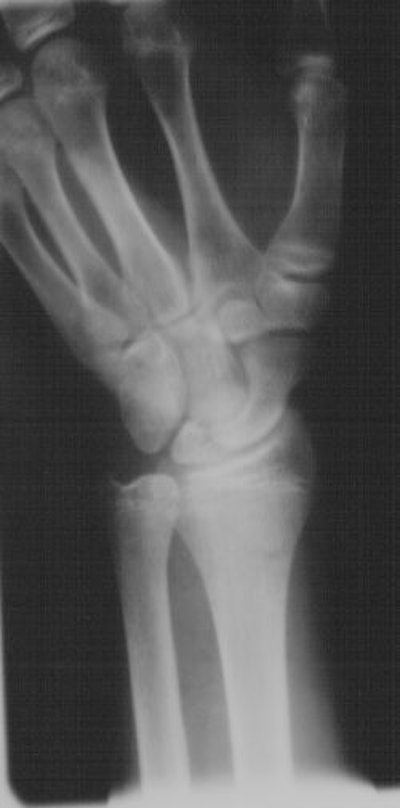

![]() |

| Six weeks post-injury scaphoid fracture. |

| Sixteen weeks post-injury and eight weeks post-application of Exogen device, there is evidence of healing. |